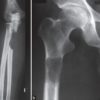

– Triệu chứng của Ewing sarcoma thường không đặc hiệu, với đau tại chỗ là triệu chứng phổ biến nhất. Đôi khi có thể sờ thấy khối mô mềm. Các gãy xương bệnh lý cũng có thể xảy ra. Các triệu chứng toàn thân bao gồm sốt có thể xuất hiện. Mức độ ESR và LDH trong huyết thanh cũng tăng cao.

– Điều trị phối hợp hóa trị liệu, phẫu thuật tại chỗ, tia xạ. 50% gặp ở thân các xương dài nên phẫu thuật khó khăn.